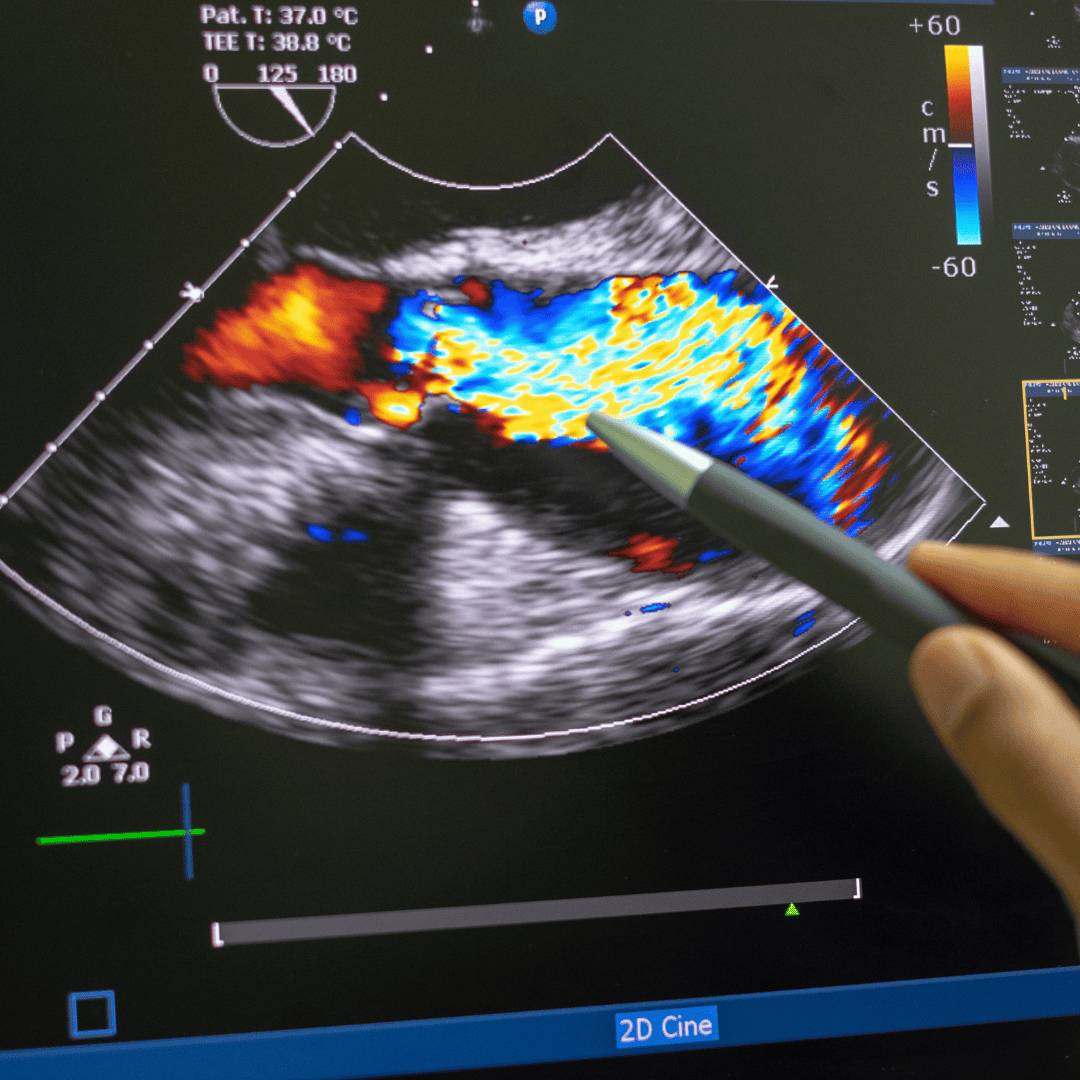

3D Echo & TEE

Advanced echocardiography and guidance for structural cases